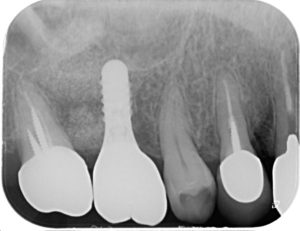

上の2枚のレントゲン写真は

根の病気が原因で保存することが難しく

抜歯した部位にインプラント治療を行なった一例です。

現在もお変わりなく使用していただいております。